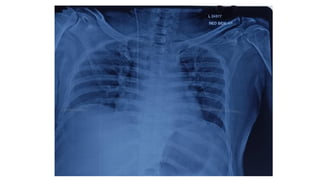

Chest X-ray